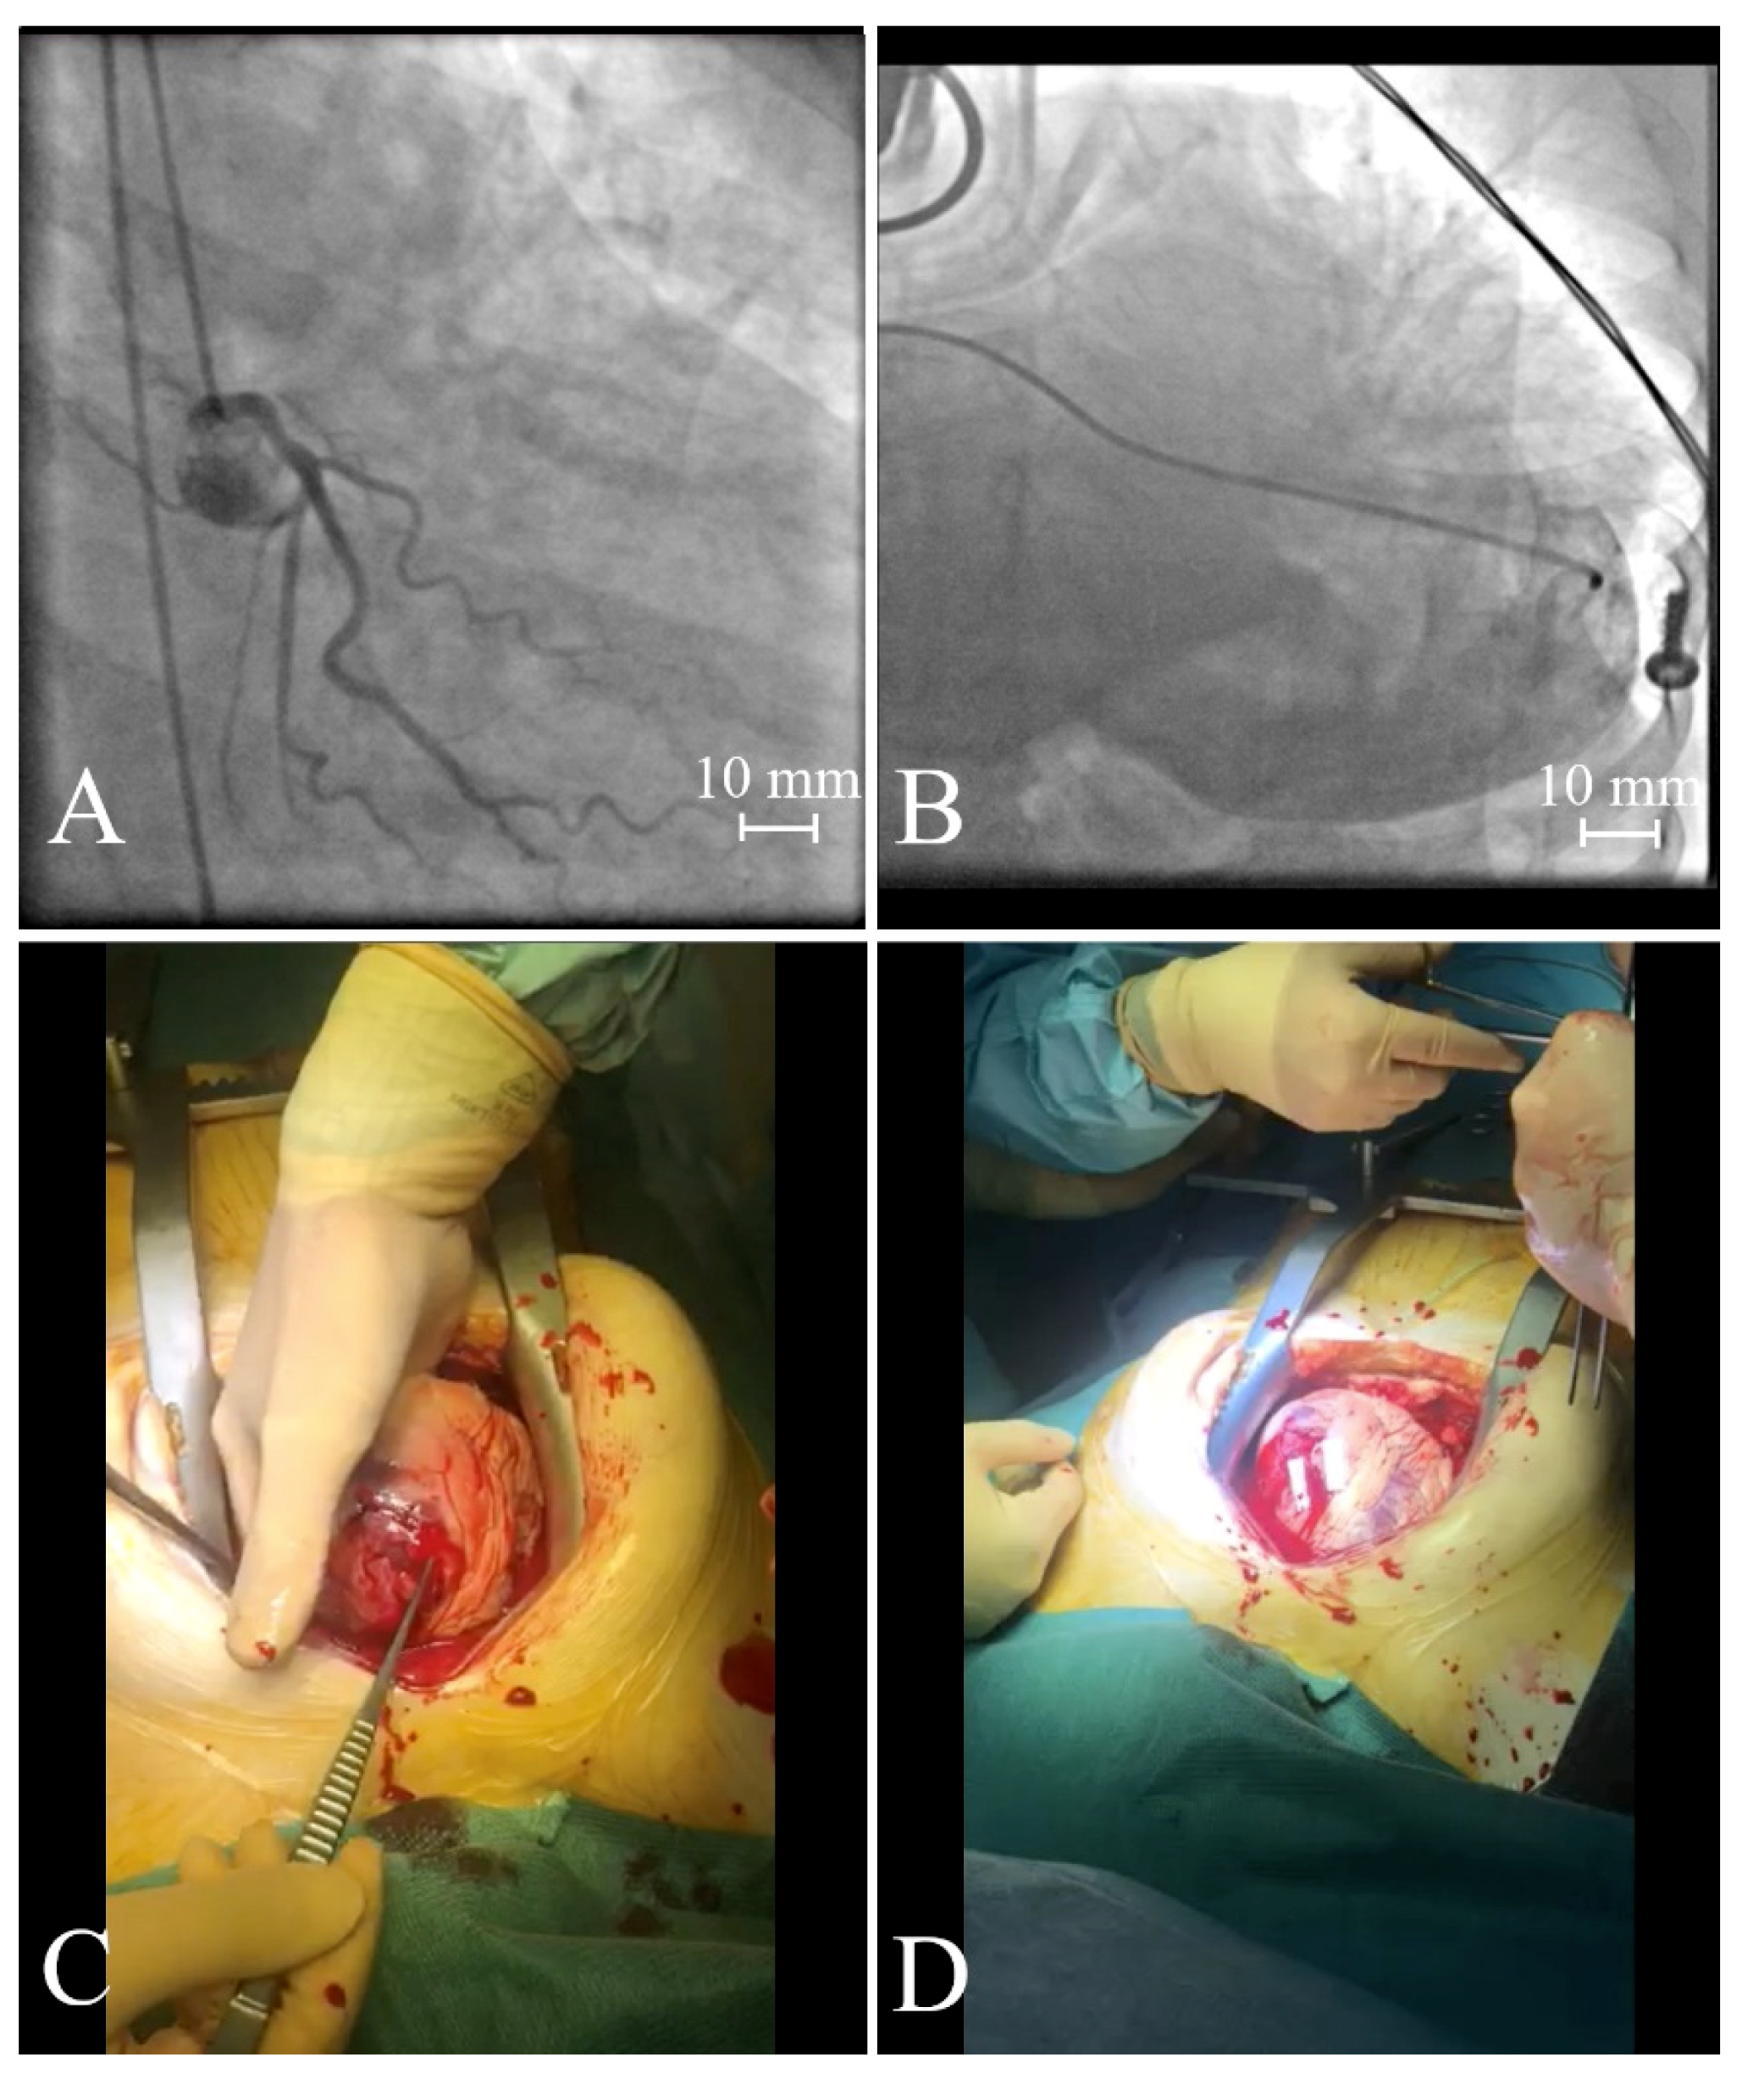

- Molek, P.; Wlodarczyk, A.; Gajos, G.; Nessler, J.; Zalewski, J. Simultaneous cardiac free wall rupture and ventricular septal rupture following acute myocardial infarction treated with emergency balloon closure. Pol. Arch. Intern. Med. 2019, 129, 830–832. [Google Scholar] [CrossRef]